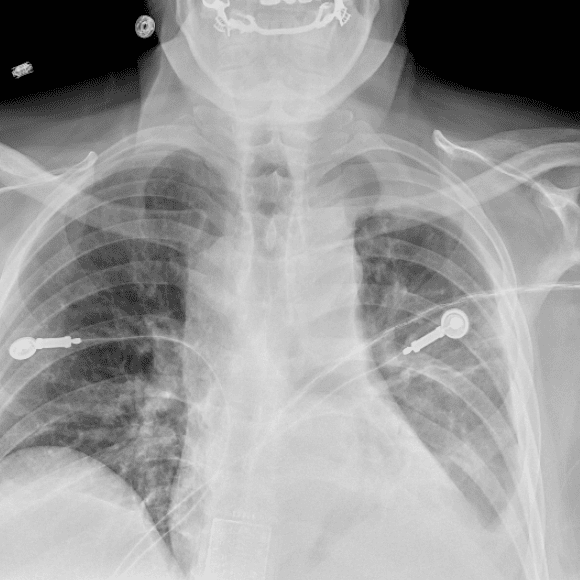

Practice Cases